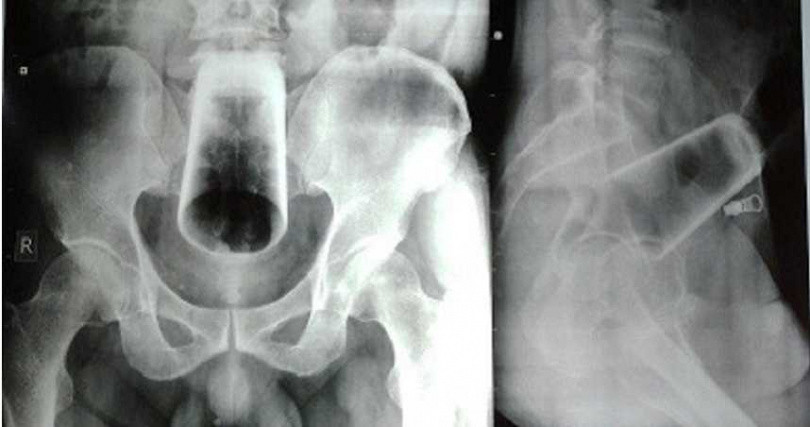

| Tấm phim X-quang cho thấy cốc nước úp ngược trong trực tràng và đại tràng. |

Bác sĩ cho biết sau khi thăm khám, tâm trạng và hành vi của bệnh nhân bình thường, không có tiền sử bệnh tâm thần, chụp X-quang cho thấy có một cốc nước úp ngược trong trực tràng và đại tràng. Bác sĩ không thể trực tiếp rút chiếc cốc ra bằng tay và lo lắng chiếc cốc sẽ bị vỡ, cuối cùng phải thực hiện phẫu thuật cắt đại tràng sigma để lấy chiếc cốc ra thành công.